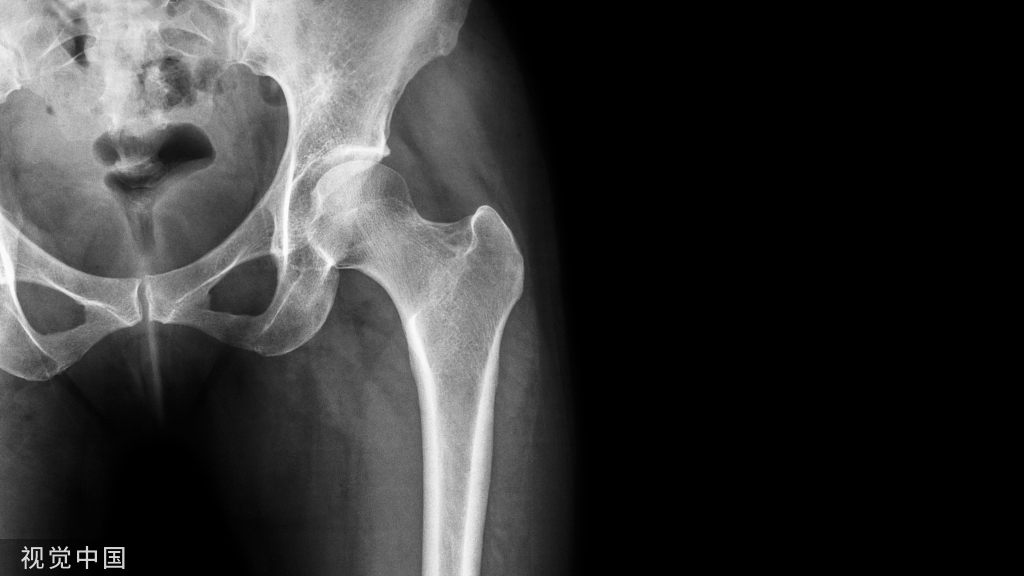

病例1:患者男,62岁,在多次左髋关节手术后,主诉左髋关节疼痛和外展肌无力。他在9年前接受了左侧全髋关节置换术,随后分别在手术后3、6和9年进行了外展肌修复术。在体检中,注意到有Trendelenburg步态。

(A-C)术前X光显示左侧股骨近端骨量减少,翻修时预先放置的模块化骨干接合股骨柄用于假体周围骨折的治疗。(D和E)在外展肌重建前进行的MRI图像显示臀中肌和小肌脂肪萎缩,股骨肌腱附着处改变。(F和G)外展肌重建18个月后的部分MRI图像显示臀中肌附着完整,臀小肌部分连续。患者报告的外展肌重建术23个月的结果包括:静息疼痛,1/10;行走疼痛,3/10;Harris髋关节评分,61;牛津髋关节评分,22。患者报告中度跛行,仅需长时间步行时需要拐杖。